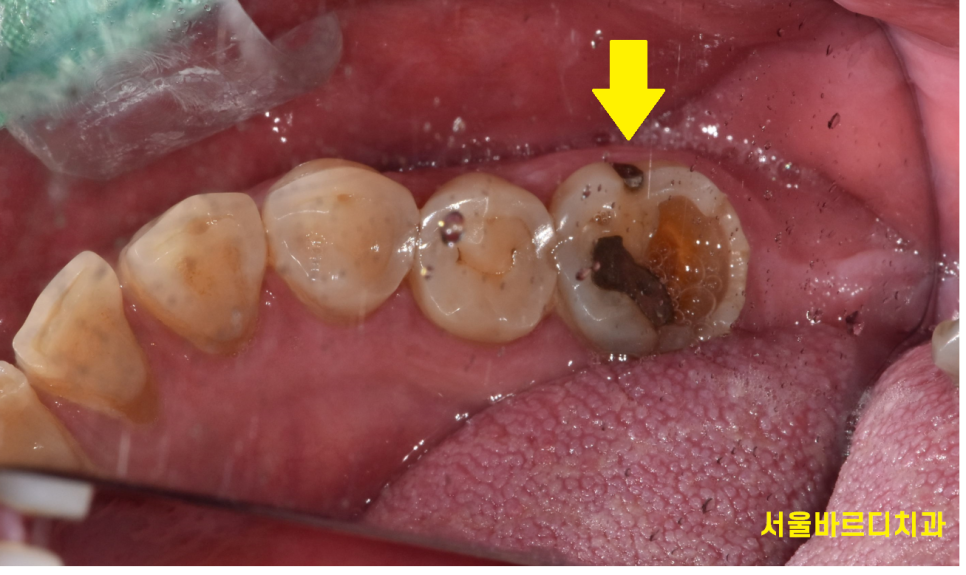

오늘 환자분도 계속된 통증으로 치아 뿌리 금이 강력하게 의심되었습니다.

그런데 이 미세 금이라는 것이ㅠㅠㅠ

뼈 안에 박혀있다보니 안보입니다.

x-ray에서는 뿌러지지 않는 이상 알 수가 없습니다ㅠㅠㅠ

환자분은 아프다고 하시는데

x-ray에서는 이상이 없어보이고 미치고 팔짝 뛰는거죠